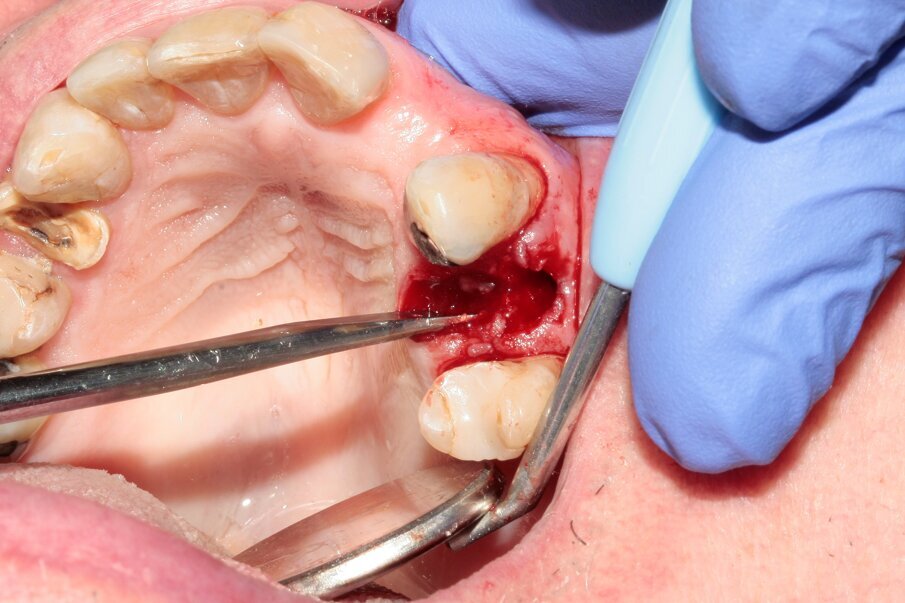

Figs. 13–15: The remains of the root were removed with the help of diamond tweezers.

By means of a gentle extraction technique, we managed to preserve the interradicular septum. Luxator P4, with its extremely sharp dual-edge blade, was used at the beginning, followed by Luxator P1 once some space had been created. Although the blades of these sophisticated instruments are reinforced with a titanium coating, they should only be used to cut the periodontal ligament and never to elevate the tooth.